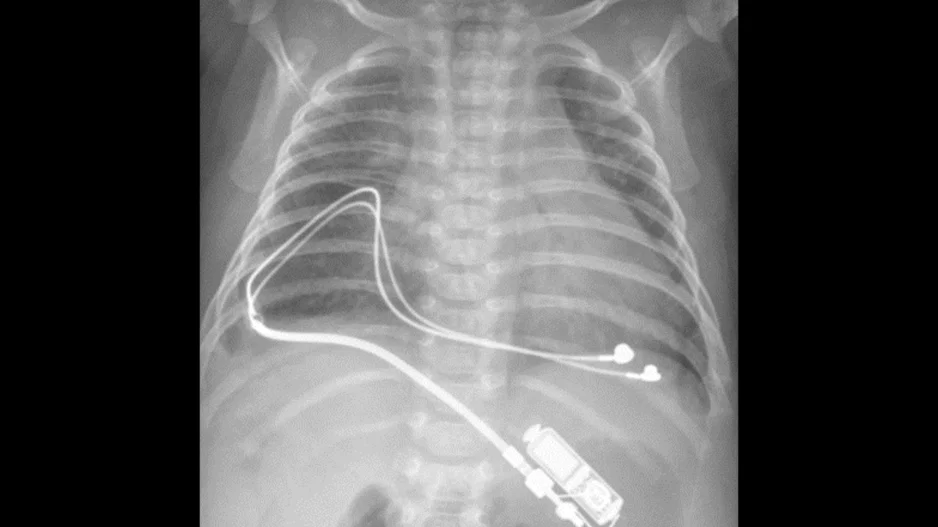

Small pacemakers built specifically for infants are both safe and effective, according to a new analysis published in Circulation: Arrhythmia and Electrophysiology.[1]

“There are two challenges with placing a pacemaker in a small…